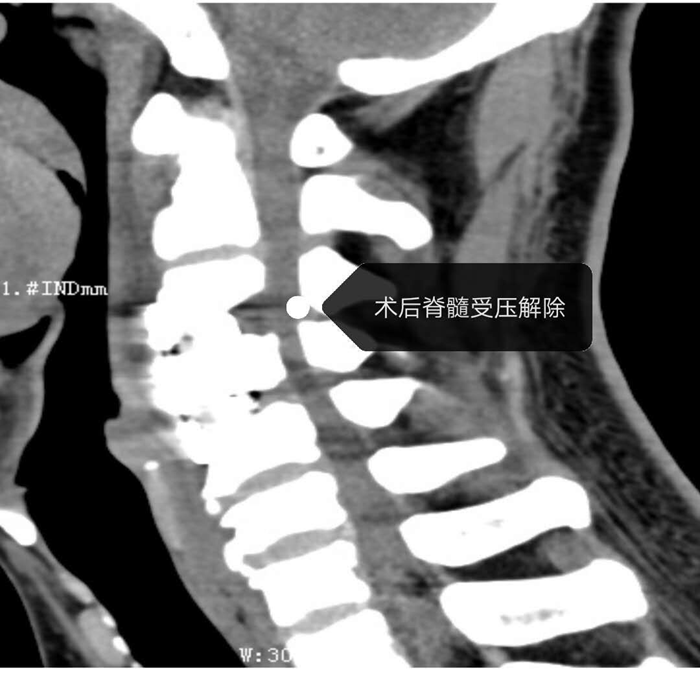

据悉,该患者因四肢麻木3月余、双下肢肌力减弱等曾辗转多地治疗,但均未见明显效果。为求进一步治疗,遂到我院疼痛科求诊。入院后科主任陈永富组织科室内讨论并邀请麻醉科吕道玲主任会诊后,在南部战区920医院李阳博士指导下由疼痛科彭杉刚副主任医师主刀下行“颈椎间盘切除椎间植骨融合术”。术程顺利,术后第二天患者即可自行下床活动,术后第三天患者诉双上肢麻木及双下肢束带感明显减轻,双下肢麻木情况改善,双下肢肌力改善。该手术的成功标志着疼痛科技术再创新高。